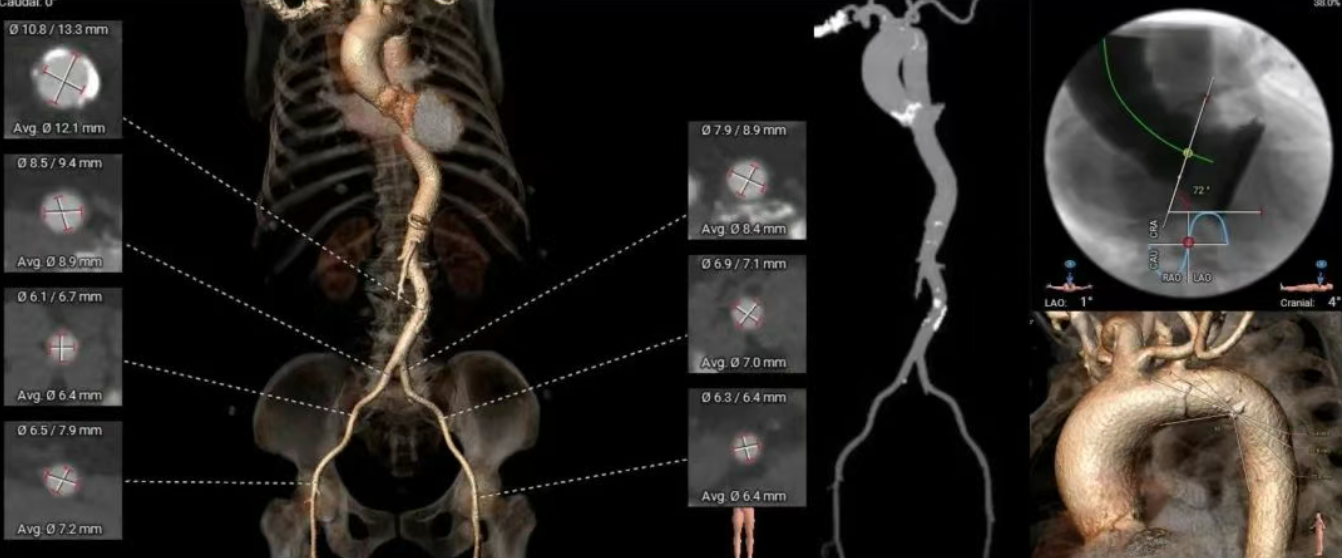

术前CT分析(79岁,男性)

▶ 功能型二叶式主动脉瓣(R-N),瓣叶增厚,重度钙化,钙化分布于左窦瓣叶及右无瓣叶对合缘,LVOT偏敞口型。

▶ 左右冠脉开口高度尚可,左窦瓣叶切线测量距离>冠脉开口下缘到根部距离。

▶ 心室腔内径尚可,心室壁厚度偏厚,心尖偏薄。

▶ 瓣环水平夹角54°,升主动脉扩张,非横位心,主动脉弓部见钙化团块,弓角偏小,弓距尚可。

▶ 外周血管内径可,血管走行稍迂曲,左右侧股动脉中分叉。

主动脉根部测量

瓣上结构测量

冠脉风险评估

LCA Height

RCA Height

左室测量

外周入路评估